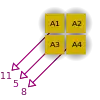

- A basic premise in back-projection is that any attenuation of the X-ray beam has occurred uniformly along the path followed from the source to the detector. Let's consider a simple tomographic slice containing just four voxels to illustrate the computational approach - see Figure 7.11. The first projection, P1 is obtained from a horizontal exposure from left to right in the figure. The back-projection of P1 involves putting the values 7 and 9 in both elements of the first and second rows, respectively. The second projection, P2 adds a 4 to the top right element, 1 to the bottom left element and 11 to the other two elements when it is back-projected. The other projections are treated in a similar fashion. Following regularisation of the data set the final image is obtained at the bottom left of the figure.

- The first estimate of the image matrix is made by distributing the first projection, P1, evenly through an empty pixel matrix. The second projection, P2, is then compared to the same projection from the estimated matrix and the difference between actual and estimated projections is added to the estimated matrix. The process is repeated for all other projections.